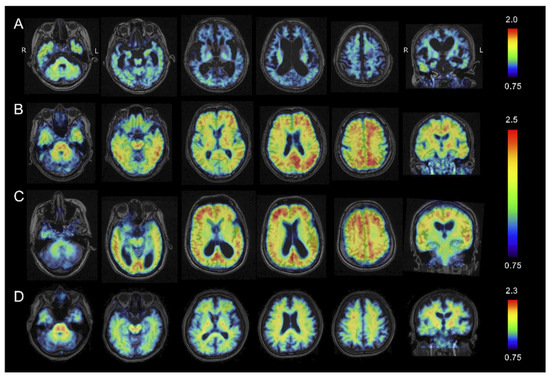

2.3. Tau PET Imaging

2.4. Amyloid β PET Imaging